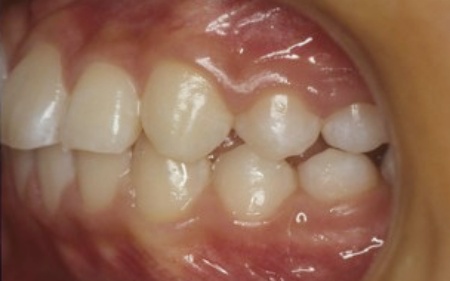

10代女性 乱れた歯並びと噛み合わせをワイヤー矯正で改善した症例

「歯並びが悪い。とくに八重歯が気になる」とご相談いただきました。

拝見したところ、上下の前歯を中心に、歯が正常な位置からずれたりねじれたりしてデコボコに生えている状態でした。

歯並びと噛み合わせを改善するために「ワイヤー矯正」を提案し、同意いただきました。

ワイヤー矯正では、治療の際に歯を動かすスペースを確保するために抜歯をするケースもありますが、患者様の場合は抜歯を行わずに治療を行うことができました。